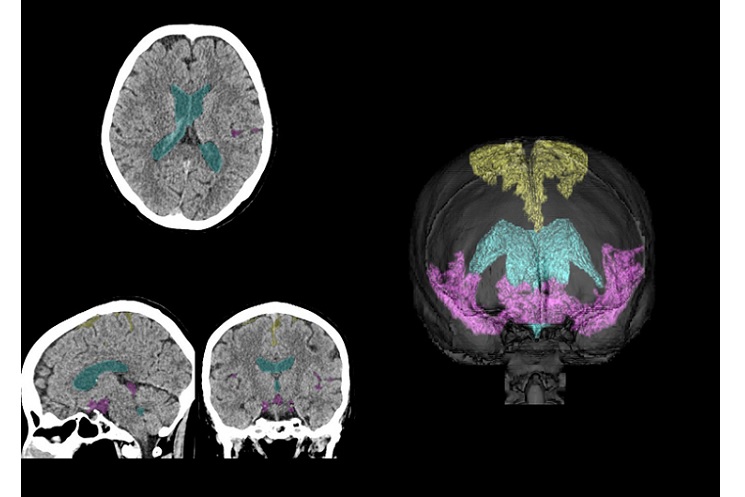

遠隔読影では、千葉大学病院の画像検査システムとビットブレインの遠隔読影システムを連携し、千葉大学病院外の放射線科医師が画像診断を行う。ビットブレインが医療用に開発した遠隔読影システムは、ネットワーク分離システムを通じて病院と遠隔読影者を接続する仕組みで、院内ネットワークと院外ネットワークを完全に分離できる。実証で膨大な検査数を抱える千葉大学病院が、外部から放射線科医が安全を確保した遠隔読影を行い、効率的に検査数を処理できるかを確かめる。